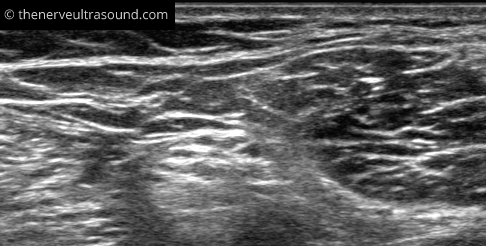

The site of the bifurcation of the sciatic nerve into the tibial and common peroneal nerve is variable. Often the portion of the sciatic nerve forming the tibial or the common peroneal nerve can be already identified much more proximal to the bifurcation.

At the popliteal fossa the main branches of the sciatic nerve are visible. The tibial nerve lies superficial

to the popliteal artery. Especially in individuals with difficult sonoanatomy it may be easier to start the scanning of the distal course of the sciatic nerve at this level; positioning of the probe in the popliteal fossa, looking for the pulsation of the artery, focusing superficial to the artery looking for the “appearance” of

a hyperechogenic structure whilst tilting the ulrasound-probe; the tibial nerve. When the tibial nerve is identified, tracking it proximally till the union with the common peroneal nerve from lateral – the bifurcation of the sciatic nerve is identified.

Another possibility is the identification of the common peroneal nerve on the fibular neck and tracking it back proximal up to the bifurcation.